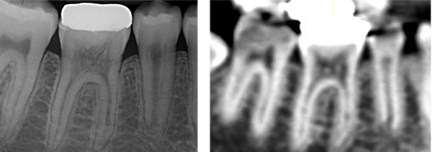

Radiographically

- Pulp is big - Pulp chamber has radiopactities – pulp is replaced by mineralised (not bone, dentine, cementum is a mix)

- RCS slightly expanded